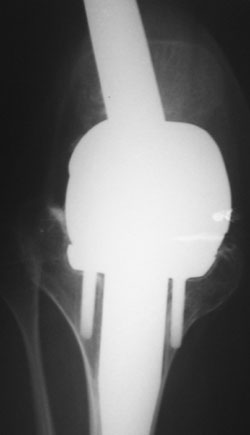

Уважаемые коллеги!У нас наблюдается пациент, 22 лет.В 1993 году -субтотальная резекция бедренной кости (остеогенная саркома -по выписке), установленэндопротез коленного сустава.

A male 22 years old sustaned subtotal resection of the femur because of osteosarcoma. A total knee

was implanted.

Is the intramedullary device seen on the AP radiograph of the hip a component of the total knee replacement or something else?

Yes, it is a long stem onco implant.